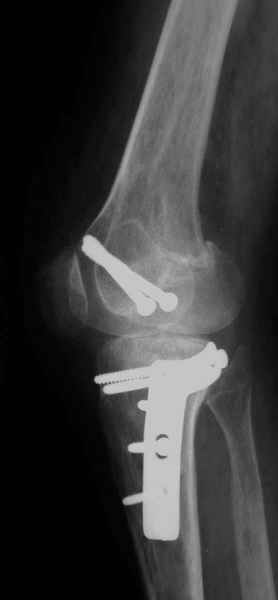

Уважаемые коллеги!На прием обратилась больная 38 лет. Травма 17.01.2005. 23.01.2005 - операция в одном из стационаров области - остеосинтез мыщелка бедра винтами, Остосинтез мыщелка большеберцовой кости L-образной пластиной.

Остальные снимки Ноябрь 2005

Иммобилизация лонгетной гипсовой повязкой 2 мес. После прекращения иммобилизации, пр начале ЛФК отмечена нарастающая вальгусная деформация конечности. Рентгенограммы в приложении. Хотелось бы узнать Ваши предложения по тактике лечения